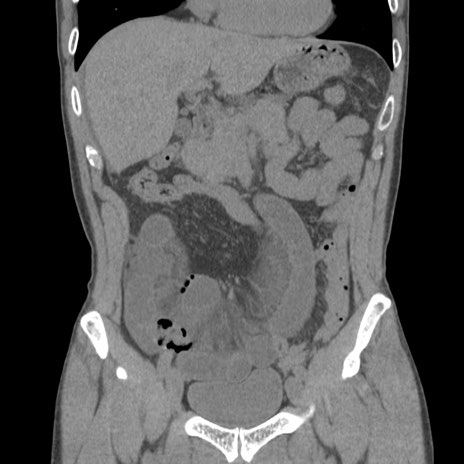

症例56 CT(冠状断像)

脂肪ウインドウ

横断像